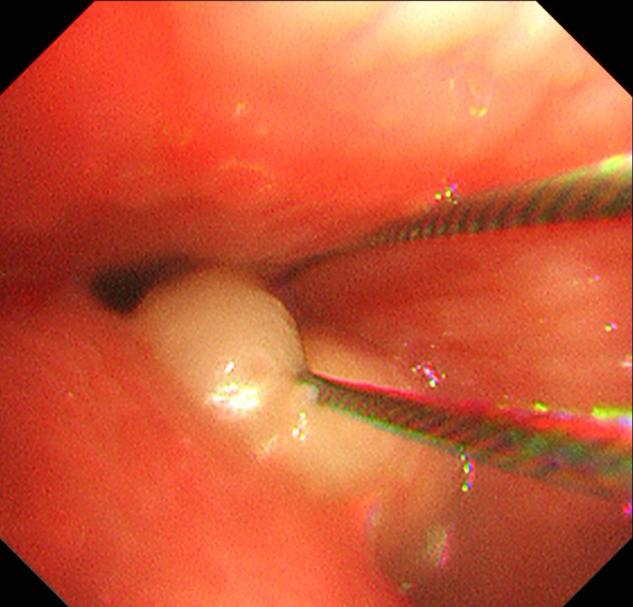

经过充分准备,呼吸与危重症医学科副主任医师詹峰为患者实施了经内镜气管内肿瘤切除术。术中,詹峰运用娴熟的内镜技术很快找到了病变,他发现患者隆突及右侧主支气管口被一新生物阻塞,气管阻塞率达90%以上。